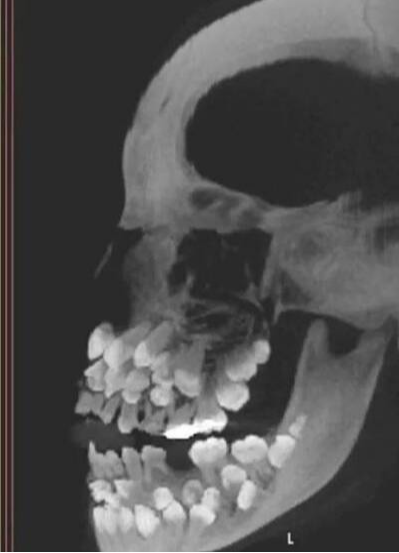

本來以為就是個簡單的拔牙小事,結果 X 光片一出來,大家都傻眼了 —— 這個 11 歲的小女童女童嘴裡居然塞著 81 顆牙!

可這、小女童倒好,18 顆乳牙賴著不走,32 顆恆牙按時報到,還額外冒出 30 多顆「不速之客」,也就是醫生說的「多生牙」。這些額外的牙齒擠在嘴裡,簡直像在搞「牙齒大聯歡」。